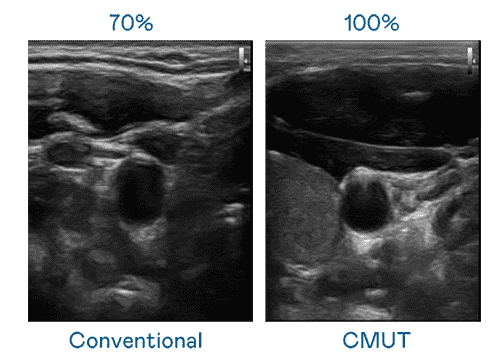

CMUT 技术是一种用电容式微机电元件来产生超音波讯号的技术。。。与传统 PZT 压电式技术相比,,CMUT 频宽增加 30%,,更宽频的超音波讯号让影像解析度大幅提升,,,,是实现高影像品质医疗超音波扫描、、、促进精准医疗发展的关键技术。。

大频宽带来超清晰影像

超音波影像的解析度高低,,,,首先取决于探头能发出的讯号频宽。。汇旺支付 CMUT 可提供高清晰的超音波讯号,,,,提供高频宽、、、、高灵敏度、、影像纹理细节更高的超音波影像,,,协助医护人员缩短影像判读时间及利用精准的医疗影像进行诊断。。。。